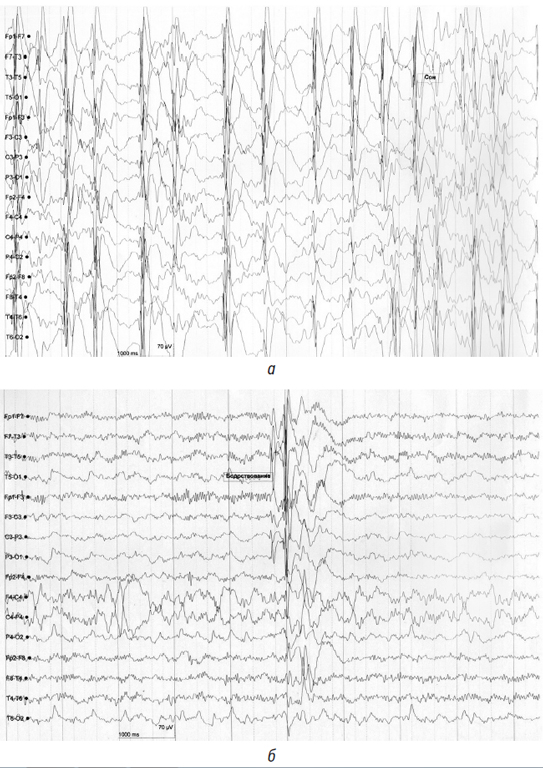

Видео-ЭЭГ-мониторирование: возрастной ритм замедлен, деформирован. Эпилептиформная активность на фоновой ЭЭГ в виде продолженной диффузной: комплексы острая волна – медленная волна с преобладанием в лобно-височных областях обоих полушарий. Сон и бодрствование слабо дифференцированы. В состоянии сна регистрируется регулярная диффузная эпилептиформная активность: высокоамплитудные комплексы острая волна – медленная волна до 90–100 % во всех стадиях сна (рис. 3 a, б).

Рис. 3. Электроэнцефалограмма пациентки: а — комплексы острая волна – медленная волна с преобладанием в лобно-височных областях обоих полушарий во время бодрствования; б — регулярная диффузная эпилептиформная активность высокоамплитудные комплексы острая волна – медленная во время сна